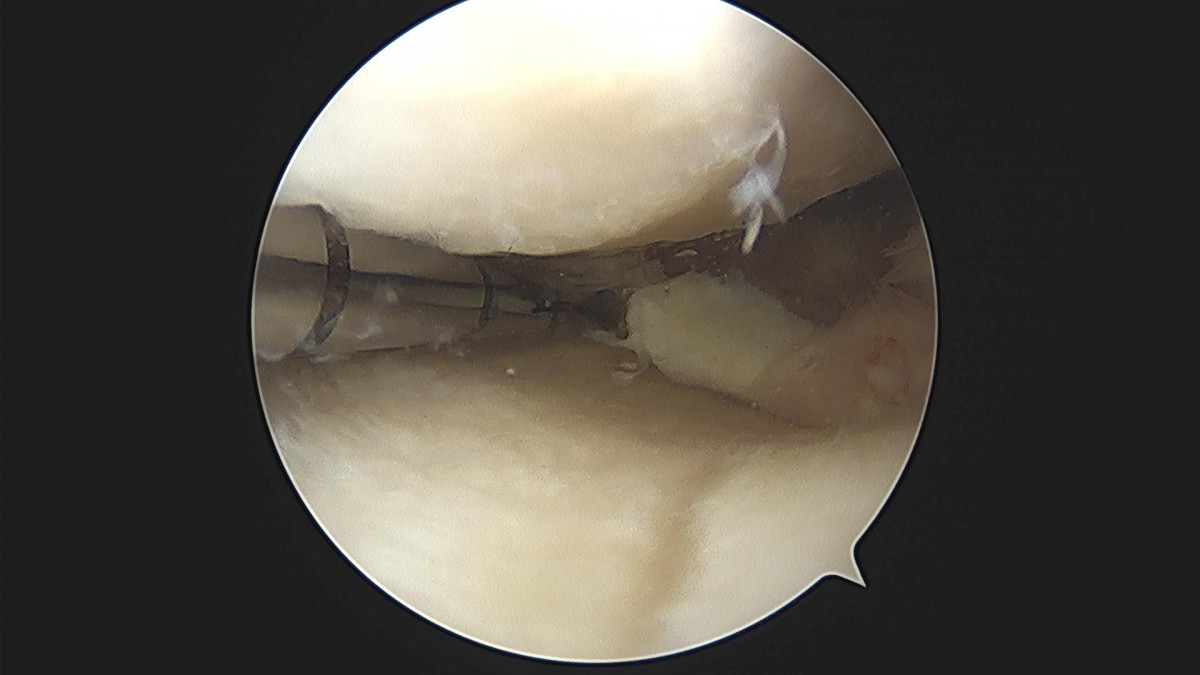

배우한원장님 무릎 내측 반월상 연골판 절제술 조명O 환자

작성자 최고관리자 댓글 0건 조회 2,228회 작성일 22-12-08 17:21